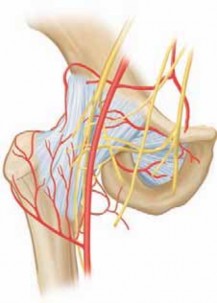

Chapter 69 Anterior Drainage of the Septic Hip in Children Richard M. Schwend DEFINITION Septic arthritis of …

Chapter 75 Bernese Periacetabular Osteotomy Travis H. Matheney and Michael B. Millis DEFINITION Hip dysplasia…

Chapter 68 Medial Approach for Open Reduction of a Developmentally Dislocated Hip Lori A. Karol and Jeffrey E…